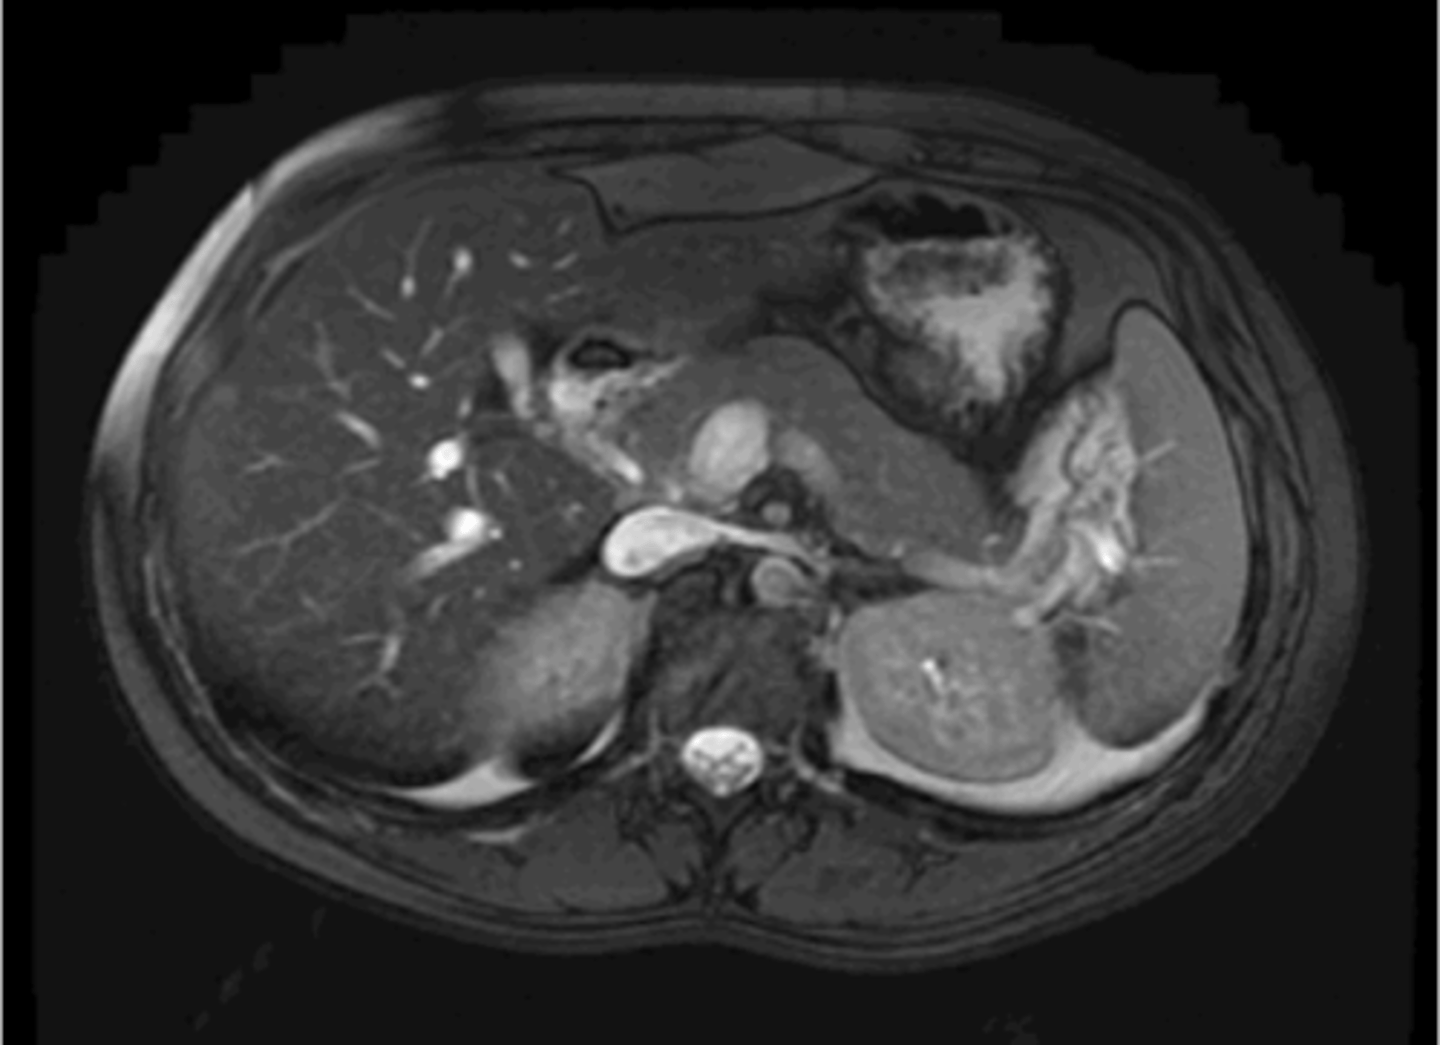

Normal pancreas CT

Normal pancreas MRI

Normal CT